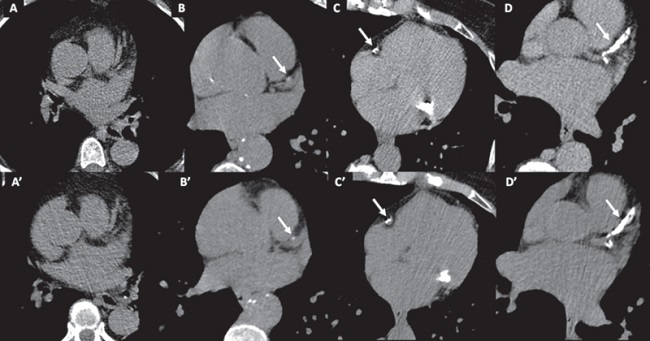

El presente fue un estudio observacional retrospectivo que incluyó pacientes a quienes se realizó una TC de tórax no gatillada de baja dosis (TCBD) de admisión realizada en el contexto de la pandemia COVID-19 y, en la misma internación y como parte de una angiotomografía computarizada cardíaca, un SCC gatillado (Figura 1). Todos los estudios fueron realizados en el mismo tomógrafo multidetector (IQon Spectral CT, Philips Healthcare, Best, Holanda). Se excluyeron del análisis los pacientes con cirugía de revascularización previa y los vasos con stents. Se evaluó la presencia de CAC y su extensión utilizando tanto variables ordinales (número de segmentos con CAC, y de forma cualitativa: ausencia, leve, moderada y grave) como variables continuas (unidades Agatston). 4 También se evaluó la extensión de calcificaciones en la válvula aórtica (unidades Agatston). El análisis cuantitativo del SCC fue realizado utilizando software dedicado (HeartBeat-CS, Philips Healthcare, Best, Holanda). La TCBD, asociada con dosis de radiación efectiva menor de 3 mSv, fue adquirida utilizando los siguientes parámetros: colimación 64 × 0,625 mm; voltaje 120 kV; corriente 70-140 mA; tiempo de rotación 270 ms; pitch 1,23; espesor 2,0 mm (incremento 1,0 mm). No se generaron reconstrucciones de mayor espesor (el SCC gatillado presenta un espesor de 2,5 mm) con el propósito de evaluar la concordancia utilizando la TCBD exactamente como es evaluada de rutina, sin alterar el flujo de trabajo. Todos los procedimientos realizados se ajustaron a la declaración de Helsinki de 1975 y posteriores adendas, y se obtuvo consentimiento informado para la utilización de datos en todos los casos.

Se incluyeron 35 pacientes (17 hombres), con una edad media de 65,9 ± 12,8 años, en quienes se realizó una TCBD y SCC gatillado entre los meses de junio y diciembre de 2020. Se identificó CAC en 25 pacientes (71%) mediante SCC gatillado y en 26 pacientes (74%) mediante TCBD (kappa 0,93; IC 95% 0,79-1). En cuanto a la evaluación cualitativa ordinal de la CAC, identificamos una buena concordancia entre los métodos, con un kappa ponderado de 0,85 (IC 95% 0,73-0,97) (Tabla 1).

Utilizando el SCC gatillado, se identificó una media de 3,86 ± 0,7 segmentos con CAC mediante SCC gatillado, comparado con 3,79 ± 0,6 segmentos mediante TCBD, con coeficiente de correlación de concordancia de 0,98 (IC 95% 0,95-0,99). La buena concordancia entre métodos respecto al número de segmentos con CAC se demostró también utilizando gráficos de Bland-Altman (Figura 2). En cuanto a la evaluación cuantitativa del SCC (unidades Agatston), se evidenció una buena concordancia entre métodos, con una mediana de 180 (rango intercuartil 0-759) unidades Agatston para la evaluación gatillada y de 164 (0-702) para la evaluación por TCBD, con CCC de 0,98 (IC 95% 0,96-0,99); con una subestimación mediante esta última estrategia del 9,8 %. El análisis de Bland-Altman demostró una buena concordancia para la cuantificación de la CAC (Agatston) en pacientes con SCC < 400 unidades Agatston, con una mayor dispersión en aquellos con calcificación muy extensa (SCC > 1000 unidades Agatston). En cuanto a la identificación de pacientes con SCC > 400, la concordancia fue buena, kappa 0,88 (IC 95% 0,72-1). Finalmente, evaluamos el score de calcio de la válvula aórtica mediante ambos métodos, y observamos una buena concordancia, con CCC 0,96 (IC 95% 0,94-0,98), expuesta, además, en el gráfico de Bland-Altman (Figura 2).